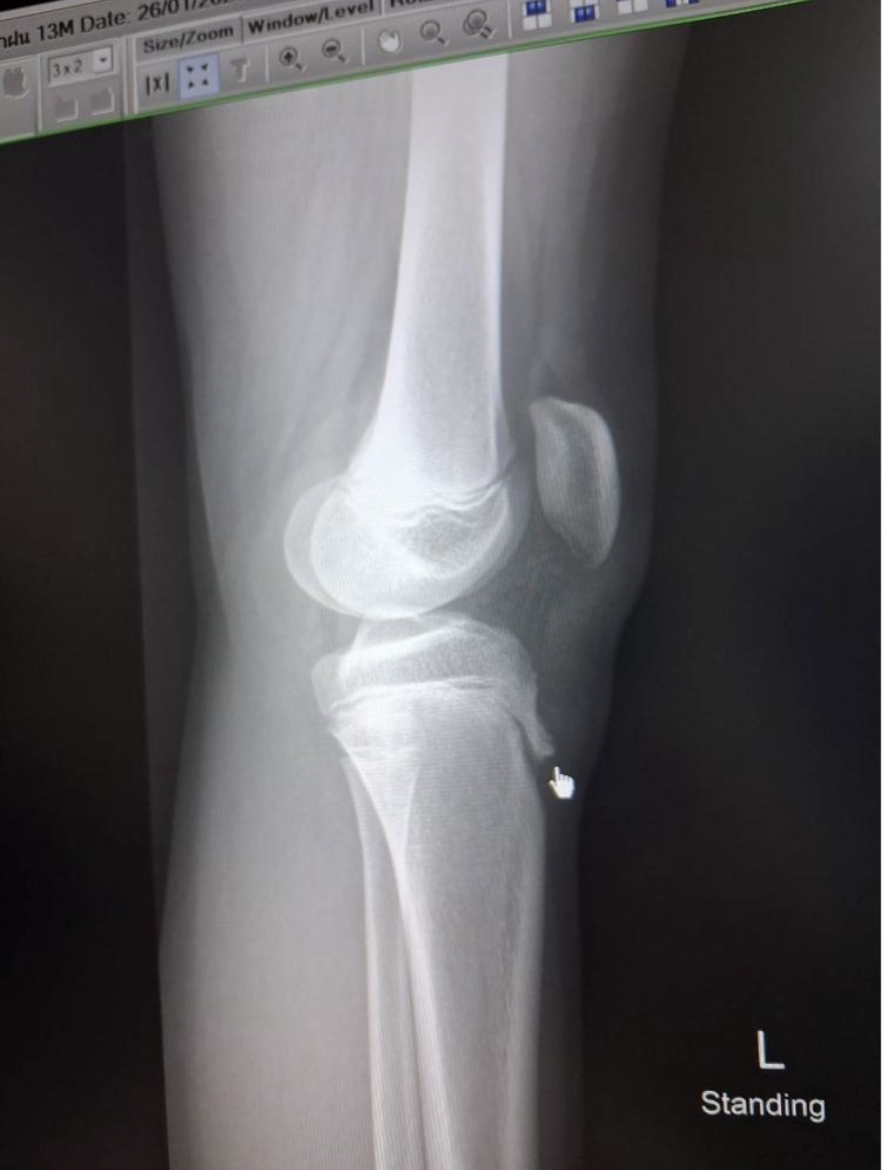

• ลักษณะอาการ: อาการเจ็บที่ปุ่มกระดูก จะมีอาการเป็น ๆ หาย ๆ มักมีอาการเจ็บมากขึ้นเวลาทำกิจกรรมบางอย่าง เช่น นั่งคุกเข่า นั่งยอง เดินขึ้นบันได วิ่ง หรือ กระโดด ส่วนใหญ่จะเป็นเพียงเข่าข้างเดียว แต่ก็สามารถเป็นทั้งสองข้าง (ประมาณ 20-50 %) การตรวจร่างกาย พบก้อนนูน กดเจ็บ ที่ปุ่มกระดูกหน้าแข้ง เคลื่อนไหวข้อได้ปกติ ไม่มีข้อบวม แดงร้อน

แม้การวินิจฉัยโรคนี้จะดูจากประวัติและการตรวจร่างกายเป็นหลัก แต่ในทางคลินิกจำเป็นต้องแยกแยะโรคที่มีอาการใกล้เคียงกัน เพื่อไม่ให้พลาดภาวะที่รุนแรง:

2. มะเร็งกระดูก (Osteosarcoma): เป็นโรคที่พบบ่อยในวัยรุ่นและมักเกิดที่กระดูกหน้าแข้งส่วนบน อาการปวดจะเกิดขึ้นต่อเนื่อง รุนแรงขึ้นเรื่อยๆ จนเดินกะเผลก ในขณะที่โรคปุ่มกระดูกหน้าแข้งอักเสบมักสัมพันธ์กับการออกกำลังกาย และถ้าอยู่นิ่ง ๆ มักไม่เจ็บ เดินได้ปกติ

3. โรคกระดูกอื่นๆ: ถ้ามีอาการปวดมากทันที เดินกะเผลก อาจต้องนึกถึง โรคอื่น เช่น avulsion fractures, Sinding-Larsen and Johansson syndrome เป็นต้น